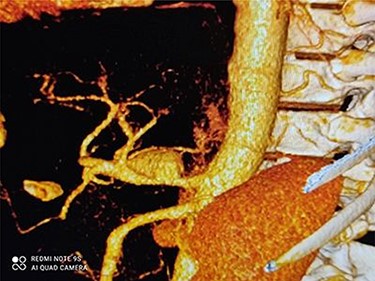

CT angiography revealed a saccular aneurysm in the right trunk of the celiac artery (42*56*59 mm) with thrombus formation lining its wall. The aneurysm lumen was patent and had a diameter of 20*21*34 mm. With a 12-mm patent neck, the aneurysm was connected to the main artery. The aneurysm was surrounded by distal branches of the left gastric, common hepatic and splenic arteries. A percutaneous angiographic intervention was suggested to the patient, and he was asked to go to NPO from midnight. After prepping and draping, a right femoral artery puncture was performed under local anesthesia, and a 6 French angiographic sheath (Arrow®) was inserted. The 6 French JR catheter (Alvision™) was extended to the aorta via a hydrophilic wire (AqWire®) and contrast media was injected, revealing a celiac artery aneurysm. The 8F*40 (Arrow®) sheath was then replaced, and the celiac artery was cannulated, and two 40*10 and 40*9 mm covered stents (Fluency™) were inserted through a stiff park wire (Amplatz Emerald). Finally, good results were obtained, with full aneurysmal coverage and distal celiac artery patency. Three days after the patient was admitted to the ward, a CT angiography revealed good results with complete coverage of the aneurysmal area and no leakage.

Figures 3 and 4 show CT angiography findings after the endovascular intervention.